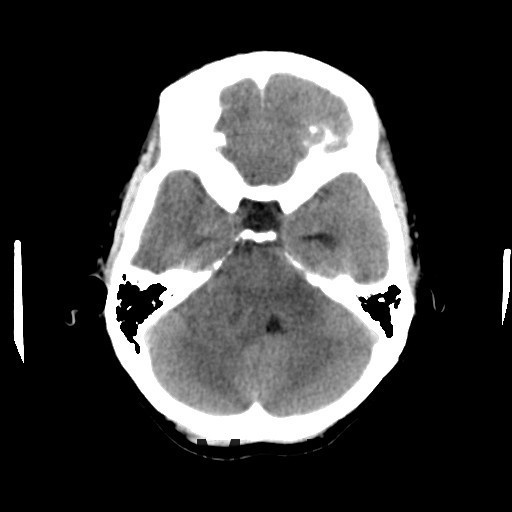

查体:神志清醒,查体合作。双眼视物模糊,眼球运动无明显异常。双侧瞳孔等大等圆,直径3mm,对光反射灵敏。 辅查:头部CT示:右侧桥小脑角区占位,考虑听神经瘤可能,并梗阻性脑积水。建议进一步MRI检查;头部MR示:右侧桥小脑角区占位,考虑为听神经瘤,并梗阻性脑积水;DTI示脑桥、桥臂及右侧桥小脑角白质纤维束受压移位。

随访:术后病理结果提示:(右侧桥小脑角处肿物)肿瘤由梭形细胞构成,可见疏区及密切,部分细胞呈栅栏状排列,细胞有异型性,核分裂可见,间质有散在淋巴细胞浸润,结合免疫组化结果,符合神经鞘瘤。 讨论:听神经瘤是桥小脑区最常见的肿瘤,也是最常见的脑神经瘤,绝大多数病理类型为神经鞘瘤。下面结合本例影像学习一下其影像表现:首先就是部位,发生于桥小脑区的占位第一反应是听神经瘤,而且和岩骨是呈锐角相交,该征象可以和发生于该部位脑膜瘤鉴别。另外,肿瘤沿听神经长如,导致内听道扩大也是一个重要征象。增强扫描可见明显强化,这可以和发生于该部位的胆脂瘤鉴别。